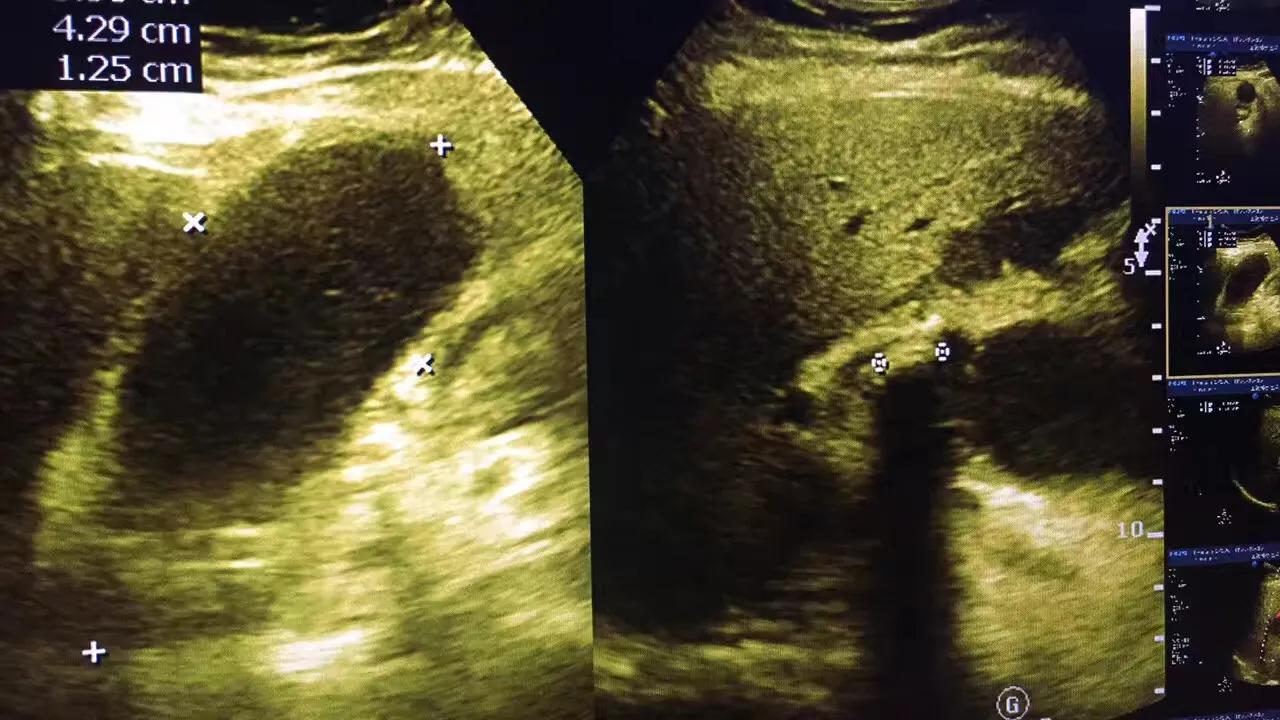

病例1.患者女性,57岁,胆囊颈部结石嵌顿继发急性胆囊炎!胆囊肿的像个茄子!